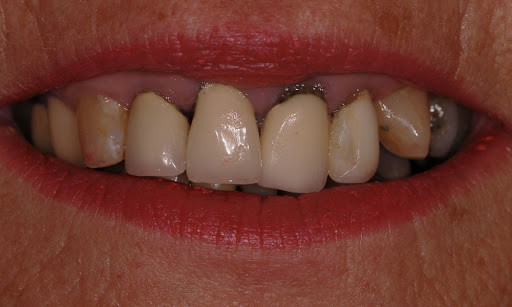

What are the different stages of periodontal disease?

Four stages of periodontal disease

Periodontal disease is broken up into four different stages, which include:

Gingivitis: This is the only stage of the disease that is reversible as it hasn’t attacked the bones yet. This is a result of plaque buildup around the teeth. Bleeding gums is one of the first symptoms you may experience. However, most symptoms of gingivitis are painless, which is what makes periodontal disease so common. Good oral hygiene and regular dental exams and routine dental cleanings can help treat and reverse gingivitis successfully.

Slight Periodontal Disease: Slight periodontal disease is the second stage of gum disease. It isn’t reversible, but can be managed. Once you reach stage two, the infection has spread to the bone and has begun to destroy bones. The bacteria have become more aggressive, which is what leads to bone less. Scaling and root planing can be used to deep clean the teeth gums. It removes deposits of bacteria that are deeply rooted in your gums.

Moderate Periodontal Disease: The third stage of periodontal disease has more probing depths, which allows for even more bacteria to attack the bones and the blood stream, too. Much like slight periodontal disease, our professional specialists will use scaling and root planing to thoroughly clean the area.

Advanced Periodontal Disease: The final stage of periodontal disease is when the infection has evolved into disease-causing bacteria. It can cause redness, swollen gums that ooze pus, sensitivity, loosening of teeth, painful chewing, severe bad breath, and bone loss. This stage requires periodontal surgery or laser therapy with the PerioLase MVP-7 TruePulse to clean the deep bacteria-filled pockets. If left untreated, stage four can lead to gaps or spacing between the teeth, the need for dentures, gum recession, and other serious health problems.

Treating periodontal disease quickly is important. At Premier Periodontics, we teach our patients good oral hygiene habits that will help them to halt the progression of their periodontal disease.